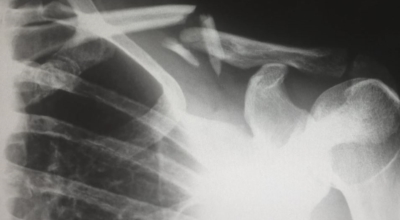

골다공증이란 단단해야 할 뼈가 약해져서 부러지기 쉬운 상태가 되는 질환을 말해요. 골다공증이란 이름 그대로 약해진 뼈에 구멍이 송송 관찰되는 모습 때문에 지어진 명칭입니다. 나이가 들어가면서 관절이 약해지고 골다공증 으로 고생하게 돼요. 골다공증은 노화때문에만 발생되는 것이 아니랍니다.

작은 쇼크을 받아도 다치기 어렵지 않고 골절이 쉽게 오는 골다공증 증상은 과한 다이어트, 음주, 흡연, 규칙적이지 않은 식생활로 젊은분들에게도 골다공증이 많이 나타나고 있습니다. 여성의 경우, 폐경 후에 여성호르몬 분비가 다운되어 골밀도가 저하되므로 뼈가 스펀지처럼 되어 골절이 쉽게 오는 것으로 보입니다. 대퇴골, 손목 척추, 발목 부위에서 주로 골절이 발생하기 때문에 평소 골다공증에 좋은 음식 또는 스트레칭, 수영, 가벼운 산책 과 같은 저강도 운동을 하시는 게 좋겠네요.